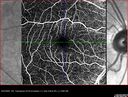

Recurrent toxoplasmosis with elevated IOP33 views48 year old man with 4 episodes over 40 years of vision loss from toxoplasmosis. His IOP was 44 on presentation.

Recurrent toxoplasmosis with elevated IOP30 views48 year old man with 4 episodes over 40 years of vision loss from toxoplasmosis. His IOP was 44 on presentation.

Recurrent toxoplasmosis with elevated IOP27 views48 year old man with 4 episodes over 40 years of vision loss from toxoplasmosis. His IOP was 44 on presentation.

Recurrent toxoplasmosis with elevated IOP26 views48 year old man with 4 episodes over 40 years of vision loss from toxoplasmosis. His IOP was 44 on presentation.